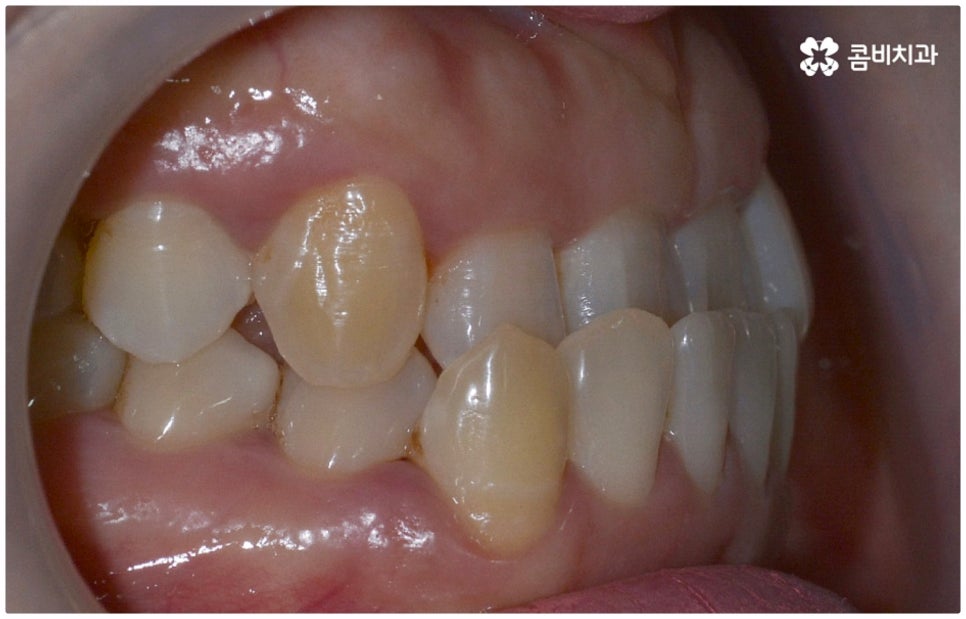

정상적인 교합은 윗 앞니가 아래 앞니를 살짝 덮는 정도로 윗니가 조금 더 앞으로 나와 있으면서 위아래 치아가 어금니까지 잘 맞물리는 것을 말하는데 반대교합은 위아래 앞니가 거꾸로 물리는 증상을 보이기 때문에 저작 활동 및 발음 조성이 원활하지 않게 되며 반대교합교정 등 적절한 치료를 받지 않고 방치할 경우 점점 더 주걱턱이 강화되는 쪽으로 뼈가 성장할 수 있어 될 수 있는 대로 빠른 시일 내에 원인을 분명하게 알아보고 그에 맞는 치료를 받는 것이 중요하다고 할 수 있어요.

골격적인 원인이 아니라면 위턱과 아래턱의 위치나 크기에는 이상이 없는데 치아의 맹출 각도 및 방향의 문제로 인해 치아가 반대로 맞물리게 된 치성 반대교합에 해당하는 경우라고 할 수 있는데요. 그 원인으로는 선천적인 치열의 문제 (아래턱 앞니 치축이 앞으로 기울거나 위턱 앞니 치축이 뒤로 들어감), 유치가 너무 빨리 빠지고 영구치가 자리를 제대로 잡지 못해 생긴 문제, 후천적인 습관 (혀를 내밀거나 손톱을 깨무는 등 치열에 좋지 않은 영향을 주는 행위를 지속적으로 반복) 으로 인한 문제 등등을 살펴볼 수 있으며, 보통 이런 경우 앞니 4~6개 치아 일부에 국한된 문제이기 때문에 보다 빠르고 간단하게 교정 치료가 가능하므로 꼭 성장기에 치료를 시작하지 않고 성인이 된 후라고 해도 비교적 쉽게 개선이 될 수 있습니다.

교정 치료가 생물학적 반응을 이용하는 것이다 보니 성장기에 진행하면 치아 이동 및 회복 속도 등에 장점이 있는 것은 분명하지만 그렇다고 해서 성인 이후 중장년 분들이 교정 치료를 받을 수 없는 것은 아니며 이미 많은 분들이 도움을 받고 계신 만큼 이에 대해서 한 번 고려해 보시면 좋을 거예요. 혹시 성장기 이후로는 양악 수술 등으로만 치료가 가능한 것이 아닐까 생각하셔서 부담스럽게 느끼셨던 분들이라면 지레 겁을 먹고 불편함을 그대로 방치하시기 보다는 검진 및 상담을 통해 적극적으로 이를 해결해 보시길 권유드리고 있어요.

물론 원인과 정도에 따라 외과적인 방법이 필요하신 분들도 있을 수 있지만 교정을 통해 얼마든지 치료가 가능한 경우도 있으며 앞서 말씀드렸던 것처럼 발전된 교정 기술 및 특수 미니스크류 등의 장치 개발을 통해 턱의 방향을 조금씩 회전시켜 원거리 치아 이동을 유발하는 것이 가능해졌기 때문에 예전에는 한계가 있었던 부정교합 케이스도 개선될 여지가 늘어나고 있습니다. 꼼꼼하게 검진을 받으시고 자신의 상황에 맞는 교정 치료를 무리하지 않게 진행하신 후 철저하게 사후 관리를 해주시면 보다 오랜 기간 동안 건강하게 고른 치열을 유지하면서 생활하실 수 있을 거예요.